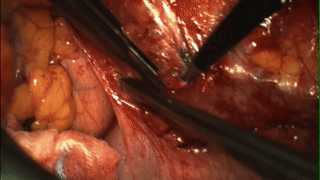

其中,針對卵巢癌的研究已進(jìn)入臨床 III 期。在一項 II 期研究中【ref.4】,研究人員在 OTL38 的引導(dǎo)下共切除了 83 處病變,其中 62 處為惡性病變,陽性率為 75%,值得注意的是,這其中又有 29% 的惡性病變無法通過普通可見光觀察到,表明 OTL38 可以提高腫瘤病灶的檢出率。

圖 5:OTL38 可在術(shù)中實時點亮卵巢癌轉(zhuǎn)移瘤【ref.4】

讀到這里,小編相信聰明的你肯定已經(jīng)注意到,在這項研究中 OTL38 有 25% 的假陽性率,也就是說有些帶有熒光的組織并不包含腫瘤細(xì)胞。研究人員在子宮和輸卵管這些健康組織中觀察到了微弱的熒光。另外,大部分患者的淋巴結(jié)也有強(qiáng)烈的熒光,其中大多數(shù)淋巴結(jié)不包含轉(zhuǎn)移瘤,可能是由于 OTL38 與表達(dá) FR-β 的巨噬細(xì)胞結(jié)合導(dǎo)致的。